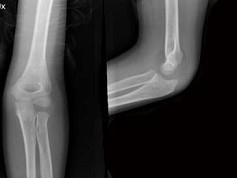

问题 8岁男孩,因外伤后感左肘关节肿痛,活动受限半小时入院,行左肘关节正侧位摄片如图示,下列哪项描述错误 ( )

选项 A、左肱骨小头骺线增宽 B、以上都不正确 C、“X”线白线不连续 D、软组织肿胀 E、“八”字征

答案 A